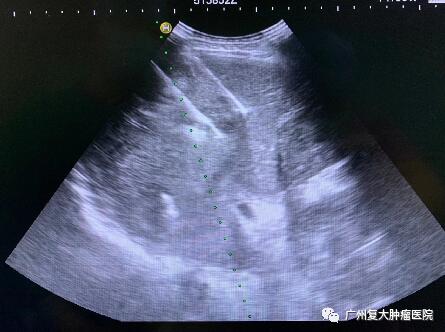

影像圖片顯示

圖2

為減輕腫瘤負(fù)荷,改善生活質(zhì)量,延長(zhǎng)患者生命,經(jīng)患者及家屬同意,我院牛立志院長(zhǎng)為其實(shí)行胰腺腫瘤、肝臟腫瘤不可逆電穿孔治療,術(shù)中以胰腺腫瘤、肝臟10個(gè)病灶為靶區(qū)消融。術(shù)后聯(lián)合化療加免疫藥物治療進(jìn)一步改善治療效果。